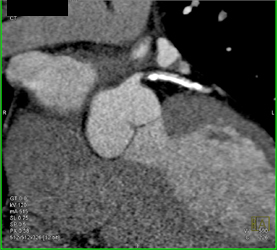

Dilated Right Atrium